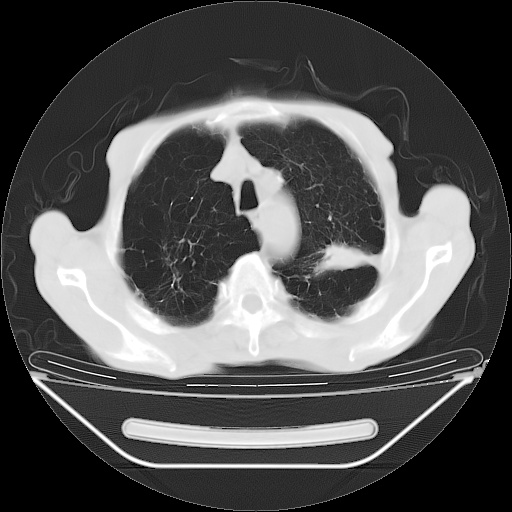

以下是引用zsl6918在2008-8-25 21:55:00的发言:[br]符合右肺周围性肺癌并肺内转移,左肺结核球。双肺肺气肿。腰椎附件转移。

以下是引用随光逐影在2008-8-25 22:03:00的发言:[br]1)考虑右肺下叶周围性肺癌并肺内转移,腰椎附件转移。2)左上肺结核(结核球形成)。3)双肺肺气肿(多发肺大泡形成)。4)双肺门区及纵隔内多发淋巴结钙化。